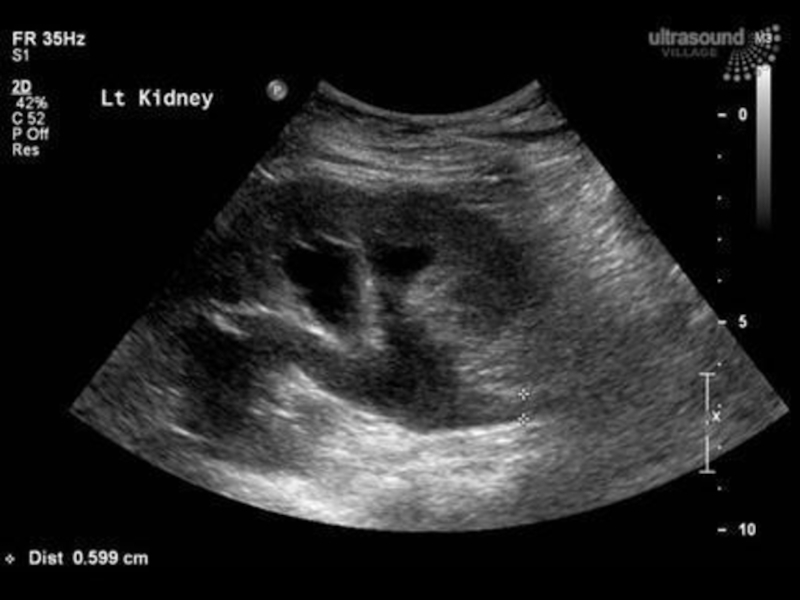

Атрезія дівочої пліви. Гематокольпос. Гематометра. Гематосальпінкс. Гострий місцевий перитоніт. Гостра затримка

сечі. Гідрокалікоз.